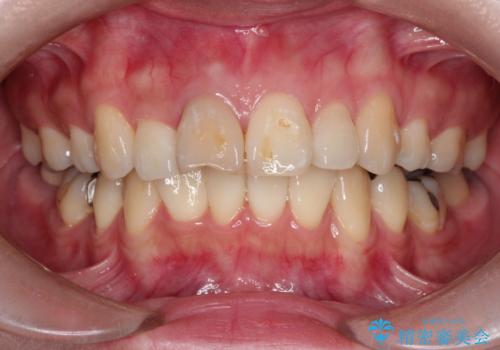

- 前歯の変色が主訴で来院した患者様です。

セラミックは、2本行う事でより自然な仕上がりとなり、患者様もご満足していただけました。